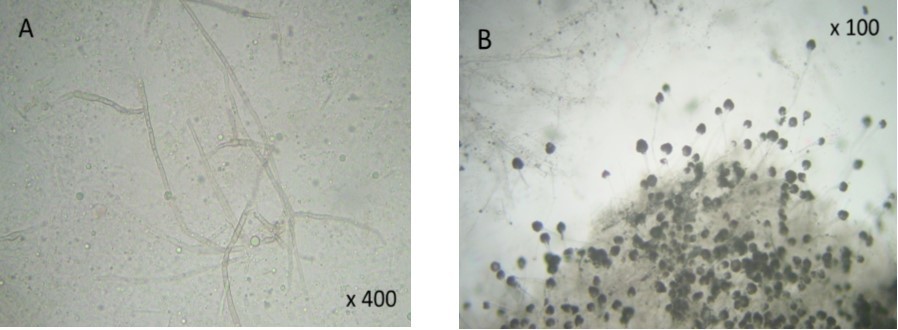

A 47 year old patient with no previous medical history presented with features of raised intracranial pressure, statokinetic cerebellar syndrome as well as left sided hemiparesis. The diagnosis of posterior fossa space occupying lesion was made. Neuroradiologic investigations demonstrated posterior fossa lesions. Magnetic resonance imaging and spectroscopy were in favor of a multiple infective process (Figure 1). Stereotatic biopsy was carried out on the patient and parasitological and histological examinations of the specimen concluded to a filamentous fungal infection of Aspergillus type. Culture and staining techniques categorized the specie as Aspergillus fumigatus (Figure 2).

Figure 2.( A) filamentous fungal infection of Aspergillus type. (B) Culture and staining techniques categorized the specie as Aspergillus fumigatus